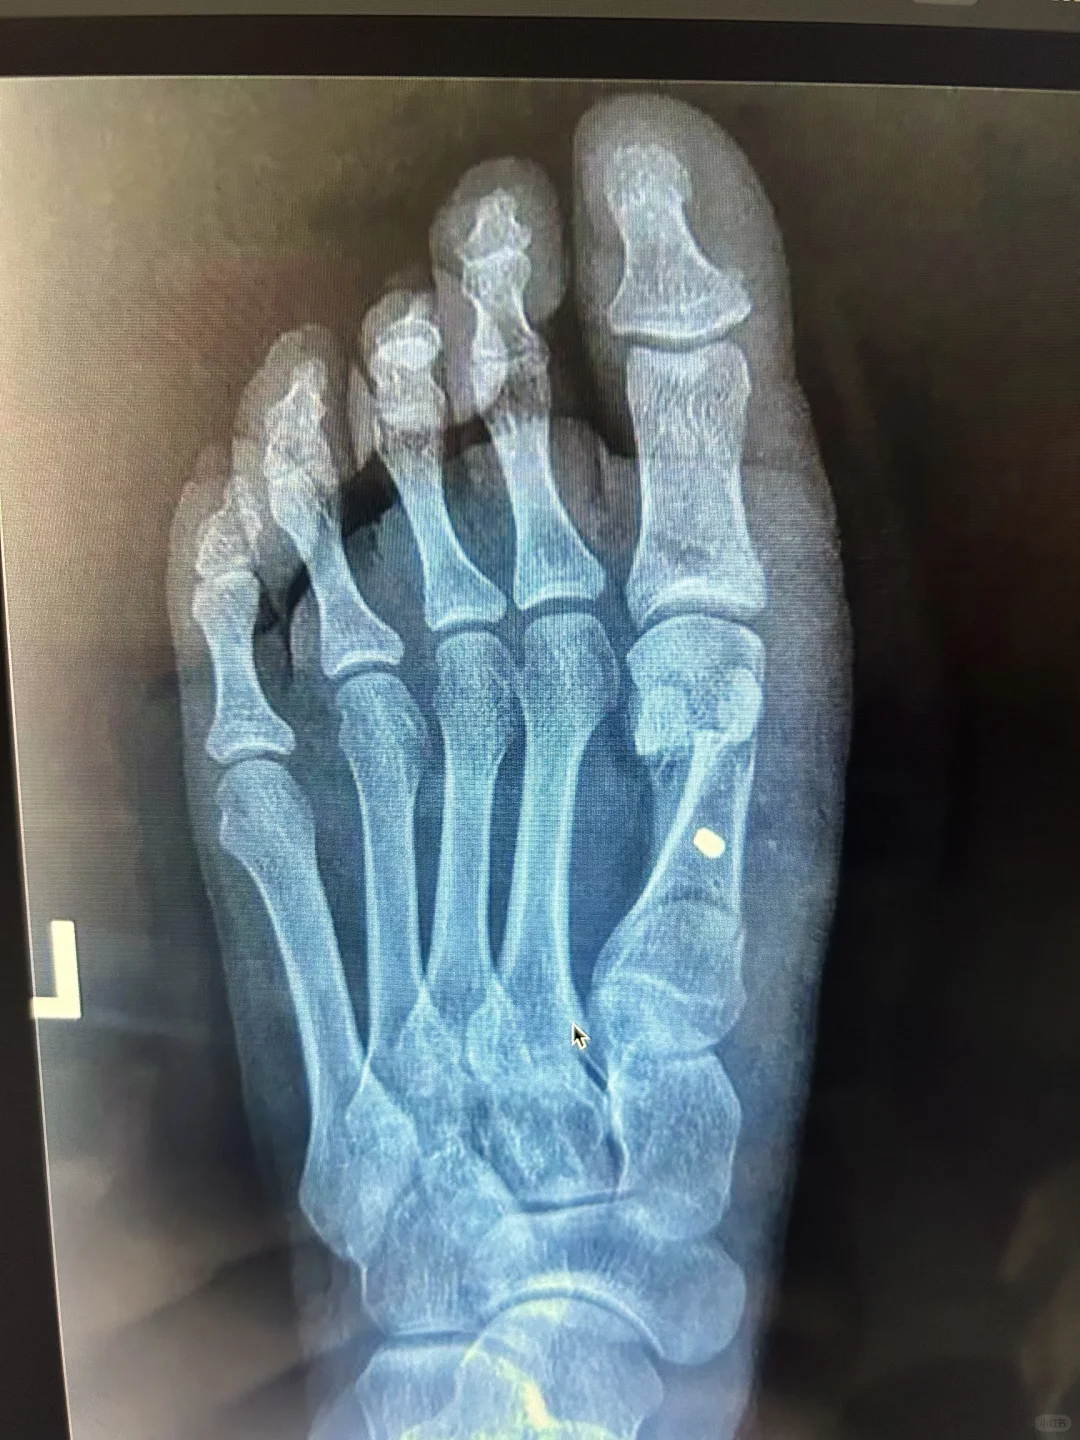

再来看图三,就是我们的旋转Scarf手术

其实,这两个方法都是把断骨放到正确的位置,而正确的位置只有一个,大家注意1.2趾的间隙,都不用夹卷,五个跖骨头距离匀称,不存在1.2比其他跖骨头更宽的问题。

对,就是用两种不同的方法,把跖骨头放到同一个位置去,当然也就获得同样的效果。

图三的方法做熟悉了,特别熟,已经形成肌肉记忆,切开还能直视下看长短高低,还能磨磨小骨刺,手术中万一位置不理想,还能拆了钉子重新拼,毕竟直视操作。上下两个大骨片也稳定。而且好多患者能接受我们的大切口。